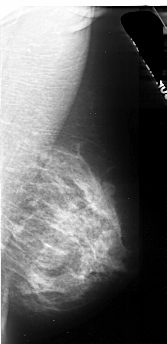

A_1104_1.LEFT_MLO

LEFT_MLO LINES 5236 PIXELS_PER_LINE 2521 BITS_PER_PIXEL 16 RESOLUTION 42 OVERLAY